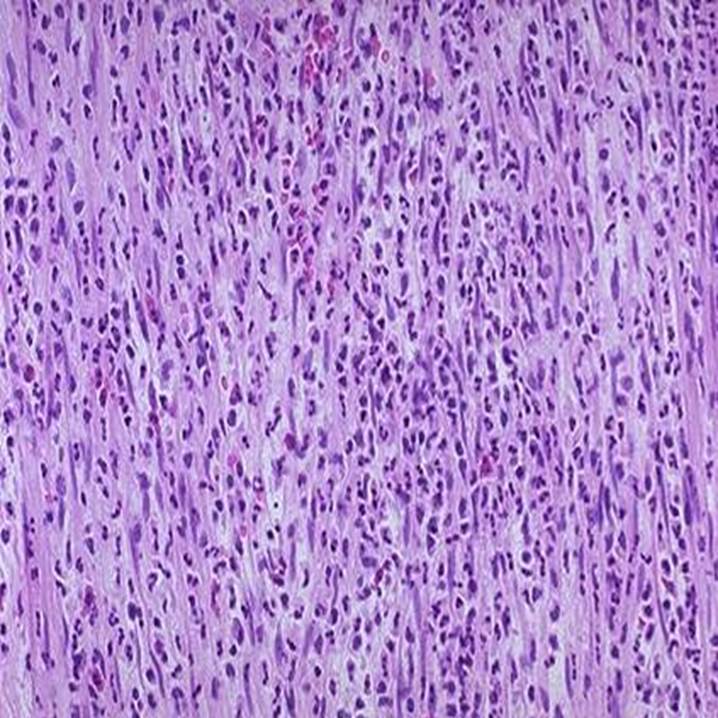

Hvilken type inflammation er der tale om på fotografiet?

Flegmonøs inflammation